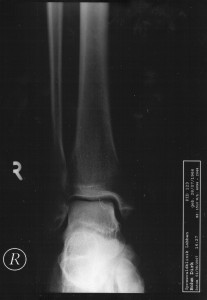

... jedoch wir kamen dort zu ganz überraschenden Urlaubsfotos. Kurz nach unserer

Ankunft begann mein rechter Knöchel ohne ersichtlichen Grund kontinuierlich anzuschwellen. Nach 1 1/2 Tagen war der Gang in die Notaufnahme unvermeidlich - und da entstanden die prächtigen Fotos.